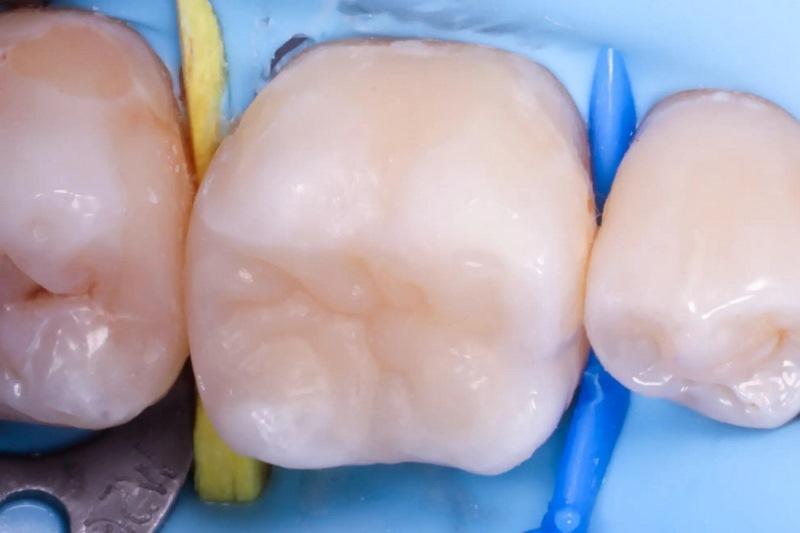

Лечение было сосредоточено на первом моляре нижней челюсти с использованием существующих композитных реставраций I и V классов (фото 1). Состояние зуба протекало бессимптомно, и фриз-тест показал нормальную реакцию. Дистальное кариозное поражение, которое не было клинически заметно, было впервые заподозрено во время планового обследования, и его протяженность была четко определена на панорамной рентгенограмме (фото 2).

Фото 1: Предоперационный снимок первого моляра нижней челюсти с композитными реставрациями.